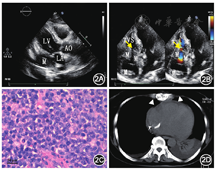

患者女性,64岁,因"反复胸闷,心悸10余天"于2018年8月28日入院。3月前因"三度房室传导阻滞"行永久性起搏器植入术,手术顺利。无吸毒史。体格检查:神志清楚,精神萎靡。颈静脉充盈,听诊两肺呼吸音减弱,未闻及干、湿性啰音。心前区无隆起,未触及震颤,心尖搏动在第五肋间左锁骨中线偏内0.5 cm处,心界略大,心率86次/min,律齐,胸骨左下缘闻及低调隆隆样舒张中晚期杂音,收缩期前增强。血压99/74 mmHg(1 mmHg=0.133 kPa)。实验室检查:D-二聚体4.43 mg/L,国际标准比值2.14,凝血酶原时间24.1 s,凝血酶原活性度60%,纤维蛋白(原)降解产物38.58 mg/L。心电图示:起搏器心律,VAT模式(超上限频率起搏器文氏方式传导);短阵房性心动过速。胸腹盆腔增强CT检查(图1)示:心影扩大,心包腔内、右心房内见多发不规则低密度肿块影,增强扫描肿块呈轻度强化。增强扫描动脉期图像显示心包内肿块包裹右冠状动脉及左冠状动脉回旋支部分节段;右心房近上腔静脉及下腔静脉入口区另见不规则无强化影;下腔静脉、肝右静脉分支内见逆流碘对比剂;右肺下叶肺动脉分支内见充盈缺损,未见明显强化。超声心动图(图2A、B)示:起搏器植入术后,右心房、左心室后壁房室沟、右心室侧壁及房室沟实性占位,伴三尖瓣机械性狭窄。临床术前诊断:右心房及心包腔多发肿瘤伴右心房血栓。于全身麻醉下建立体外循环支持,因下腔静脉解剖暴露困难,转自升主动脉、上腔静脉和右侧股静脉插管。术中探查所见:心包粘连严重,右心收缩较差,右心房为著。切开右心房可见近上腔静脉及下腔静脉入口区附着大量血栓,冠状静脉窦及三尖瓣附近见分叶状肿物突入右心房内,表面覆有炎性肉芽样组织,右房室口被肿瘤部分阻塞,三尖瓣活动受限未见受累。遂行右房肿瘤切除术+右房血栓清除术。切除右房内肿瘤及炎性肉芽样组织,清除右房内血栓。手术顺利。术后病理提示右心房肿瘤活检提示高侵袭性大B细胞淋巴瘤,符合Burkitt淋巴瘤(图2C)。免疫组织化学结果:肿瘤细胞CK(-),LCA(+),CD20(+),CD19(95%+),CD79a(+/-),CD3(T细胞+),CD10(小于5%),BCl-6(50%),MUM-1(70%),Ki-67(90%),C-MYC(60%),P53(++),BCL-2(60%),CD5(T细胞+)。肿瘤表面炎性肉芽肿样组织见大量多核巨细胞与密集的淋巴细胞浸润。术后患者接受抗凝治疗与CHOP方案(环磷酰胺+表柔比星+长春地辛+地塞米松)化疗。术后7周胸部CT显示心包内肿块较前显著缩小(图2D),症状已获得部分缓解。目前患者行周期性化疗中,一般状况良好。

本例患者术前增强CT图像具有一定特征性。CT图像显示心脏病变累及范围虽较为广泛,但心包内、右心房肿块强化呈轻度均匀强化,同时可见心包内轻度强化肿块包裹右冠状动脉及左冠状动脉回旋支的部分节段,呈血管淹没征象。血管淹没征象是淋巴瘤典型的影像表现之一。超声心动图及CT图像显示右心房三尖瓣口处的肿瘤术中证实单纯机械梗阻右房室口,未累及三尖瓣。而CT图像上近腔静脉开口区的不规则无强化影,手术证实为肿瘤导致的心房机械性梗阻而形成的附着于心房壁的血栓。本例肺动脉栓塞的栓子在增强CT上无明显强化,而瘤栓常出现不同程度强化,由此推测患者肺动脉内栓子更可能是脱落自右心房的单纯血栓。增强扫描动脉期碘对比剂逆流至下腔静脉、肝右静脉分支,Roth等[4]称此为"分支静脉对比剂淤积征",是心脏骤然停搏的CT增强表现[5],为右心房占位引起的右心房高压、右心房泵血功能不足所致。本病需与心脏血管肉瘤进行鉴别。心脏血管肉瘤通常比淋巴瘤更具侵袭性,累及心脏更大的范围,甚至穿透瓣膜、侵犯血管,同时在增强CT上趋向于显著强化,并常伴有坏死。

心脏原发性淋巴瘤通常预后不良,中位生存时间约12个月[6],诊断延误是一主要影响预后的因素。鉴于肿瘤的迅速进展和严重的器官浸润,心脏淋巴瘤甚至被认为是一种急性肿瘤。本例患者通过临床症状及影像表现明确心包腔、右心房肿瘤伴右心房、右肺动脉血栓形成的诊断后,积极进行了右心房血栓清除与减瘤手术,解除了右心房梗阻。术后患者接受抗凝治疗及化疗,患者临床症状缓解,凝血功能恢复正常,心包内肿块亦见显著缩小,目前仍在随访中。